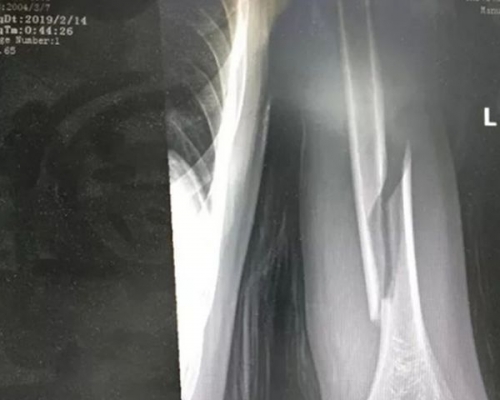

江蘇蘇州市一名14歲少年,早前與父親玩「拗手瓜」時,對方疑用力過猛,導致他的手臂被拗到肱骨骨折。

事發於上周四(14日)凌晨,少年與父親再到蘇州市立醫院求醫。少年不但神情痛苦,其左臂亦以奇怪的姿勢彎曲,並指手臂麻痹及疼痛。醫生經初步檢查後,發現少年的左臂為螺旋性骨折。醫生指,肱骨是人體上肢中最堅硬的骨骼,而且一般肱骨骨折多為橫斷性,而非螺旋性,而且一般出現在工傷事故中。可見少年在事發時,受過非常大的外力。

少年在接受手術後,已無大礙,但由於骨折時部份神經受損,手部能否恢復百分百功能,仍需進一步觀察治療。少年的父親指,父子二人當時因睡不着而玩拗手瓜,誰料他在發力的一瞬間,兒子的肱骨就意外折斷。